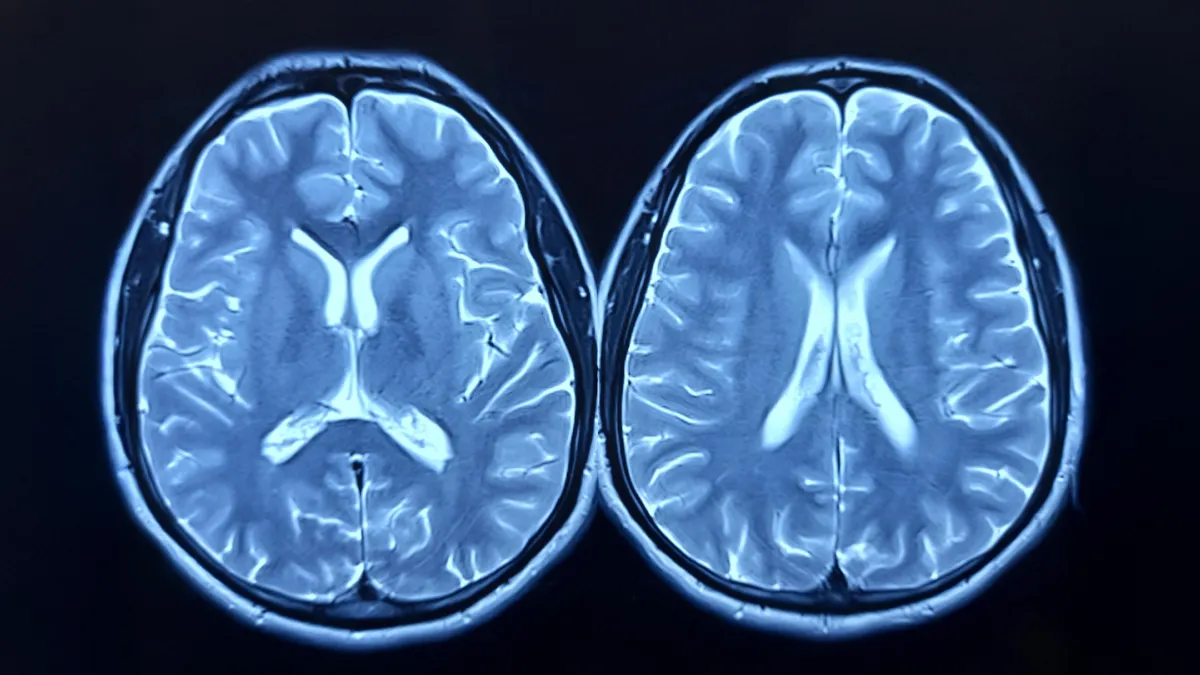

Зерттеу Nature Communications журналында жарияланды және оған шамамен 1000 дені сау ересек адамның бойлық (ұзақ мерзімді) МРТ деректері пайдаланылды. Ғалымдар қатысушылардың миын пандемияға дейін және кейін салыстырып, «ми жасы» атты көрсеткішті жасанды интеллект әдістерімен есептеді. Бұл көрсеткіш адамның шынайы жасымен салыстырғанда, оның миының құрылымы мен функциясы қаншалықты «қартайғанын» көрсетеді.

- Ми қартаюының үдеуі пандемия кезеңінде, тіпті COVID-19 жұқтырмаған адамдарда да байқалды.